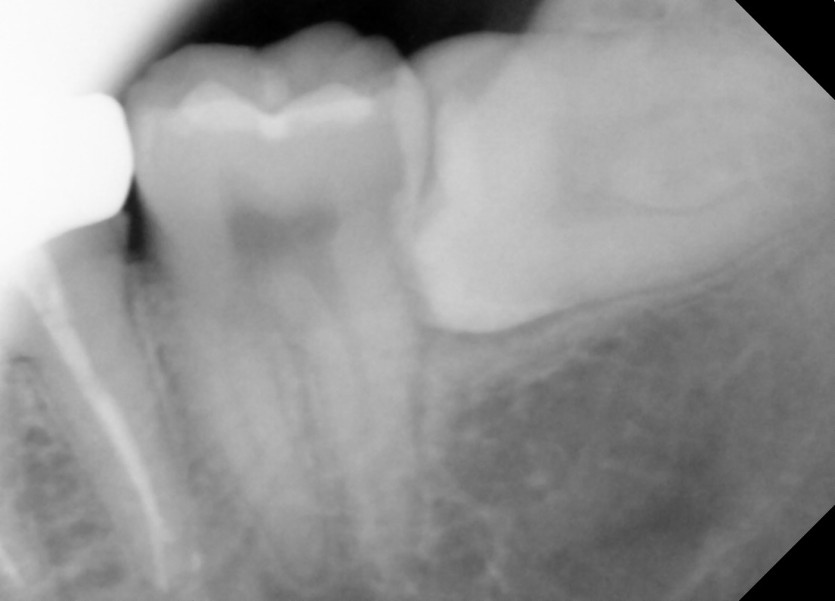

#28,38 사랑니 발치

구강 외과 전문의가 당일 발치했습니다.